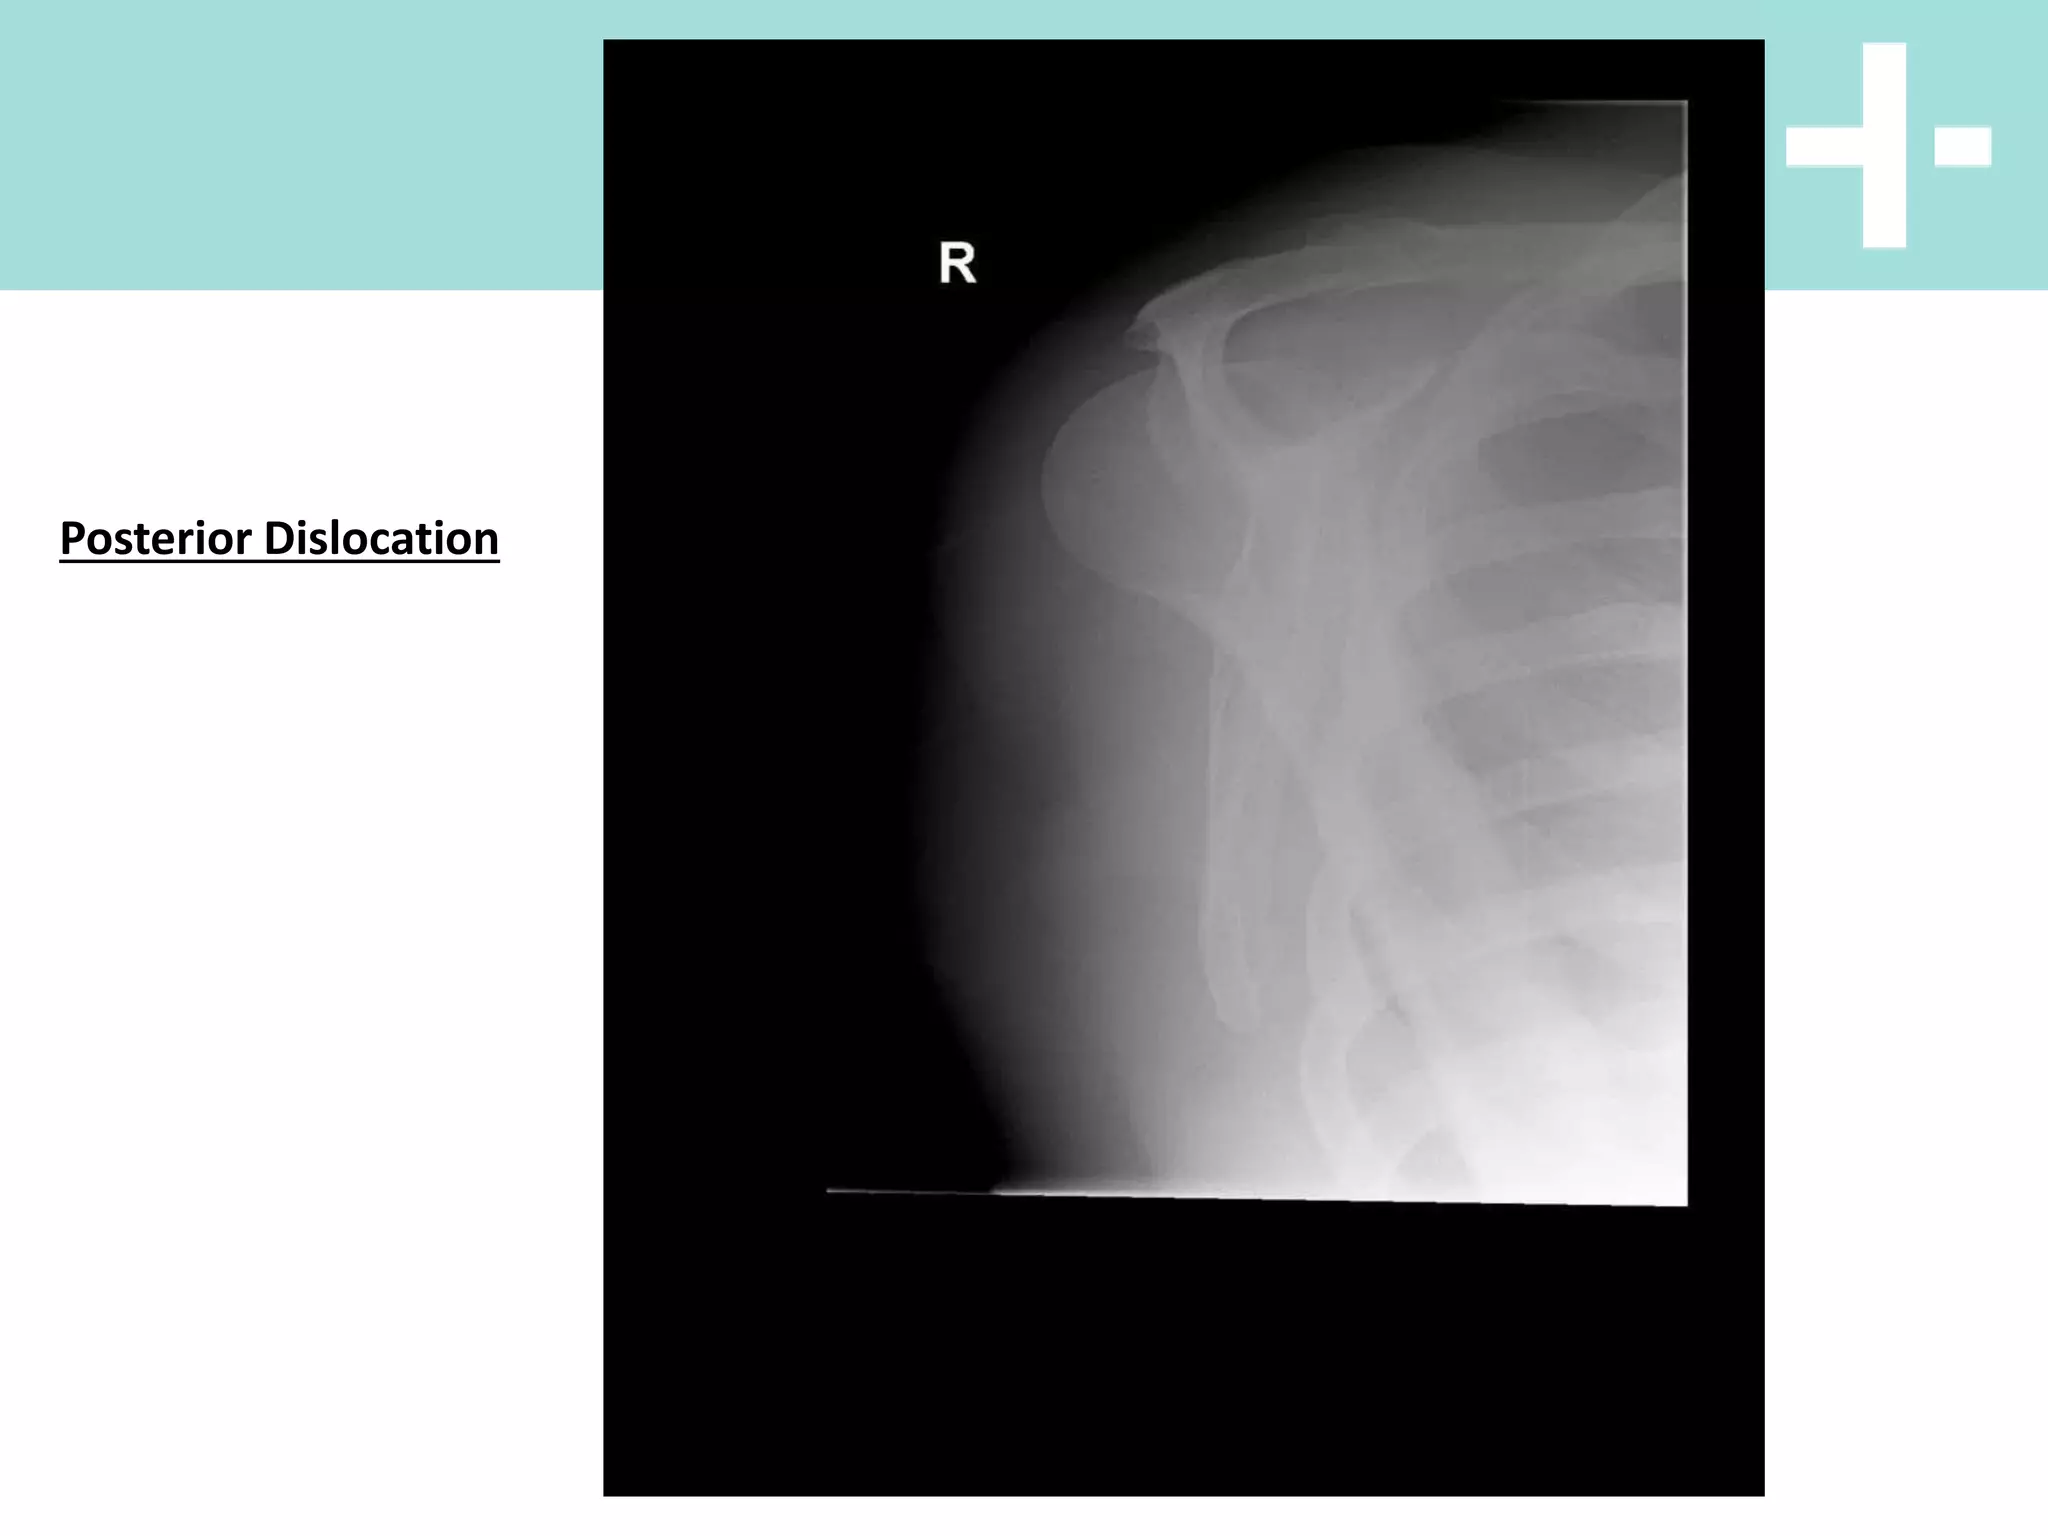

Posterior Dislocation

X Rays

Posterior

• axial loading of the IR, Adducted shoulder

OR

• violent muscle contraction (eg.

seizure/electric shock) due to powerful IRs

overcoming weak ERs